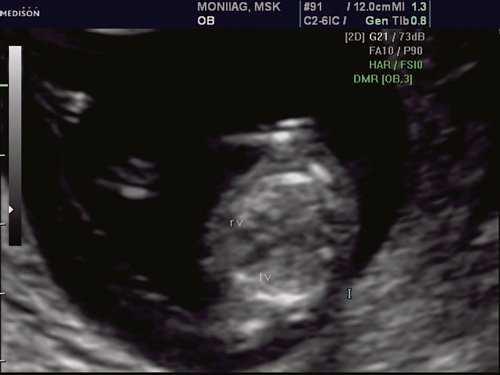

При эхокардиографии изучались четырехкамерный срез сердца плода (рис. 1) и срез через три сосуда (рис. 2). УЗИ проводилось трансабдоминальным датчиком, лишь при необходимости (затрудненная визуализация) использовался внутриполостной датчик. Четырехкамерный срез сердца плода при ультразвуковом сканировании трансабдоминальным датчиком визуализировался в 85% случаев, срез через сосуды - в 73%, при использовании трансвагинального датчика эти цифры существенно возрастали до 100 и 91% соответственно. Оптимизация пренатальной диагностики ВПС может быть достигнута путем строгого соблюдения основных методических правил. При оценке четырехкамерного среза плода необходимо оценить нормальное расположение сердца плода, исключив его эктопию (рис. 3), положение оси сердца плода, что не представляет никаких трудностей, нормальные пропорции и размеры камер сердца, движение створок атриовентрикулярных клапанов должно быть свободным, септальная створка трикуспидального клапана должна располагаться ближе к верхушке сердца (рис. 4). При оценке среза через три сосуда необходимо оценить взаиморасположение сосудов и их диаметр.

Рис. 1. Беременность 12 недель. Четырехкамерный срез сердца плода. Отчетливо видны камеры сердца.